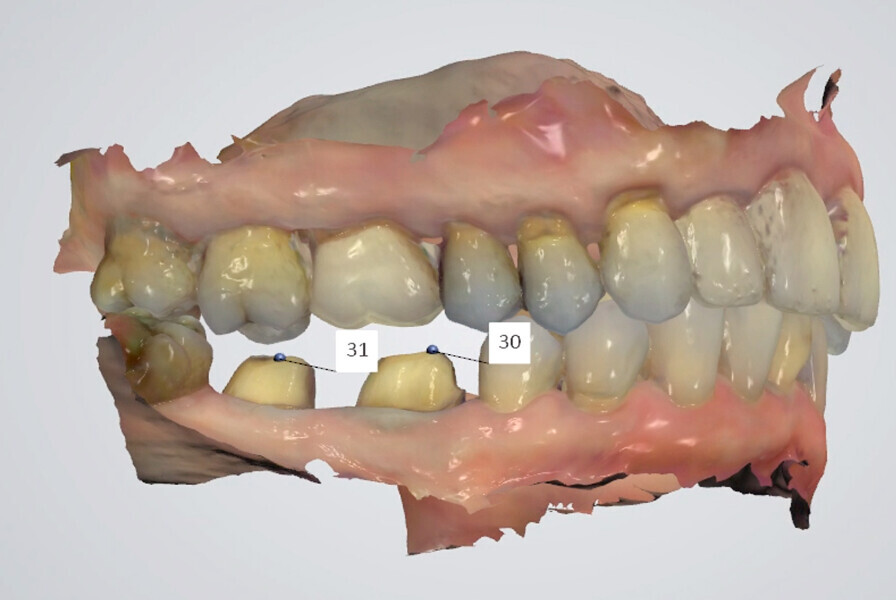

Fig. 18: TRIOS 3 software (3Shape) matching digital casts of arches to side view inter-arch scan (in light blue).

Fig. 19: Occlusal record limited to the prepared tooth area (when existing intercuspation is not altered).

Fig. 20a: Digital recording of intercuspation.

Fig. 20b: Digital recording of intercuspation.